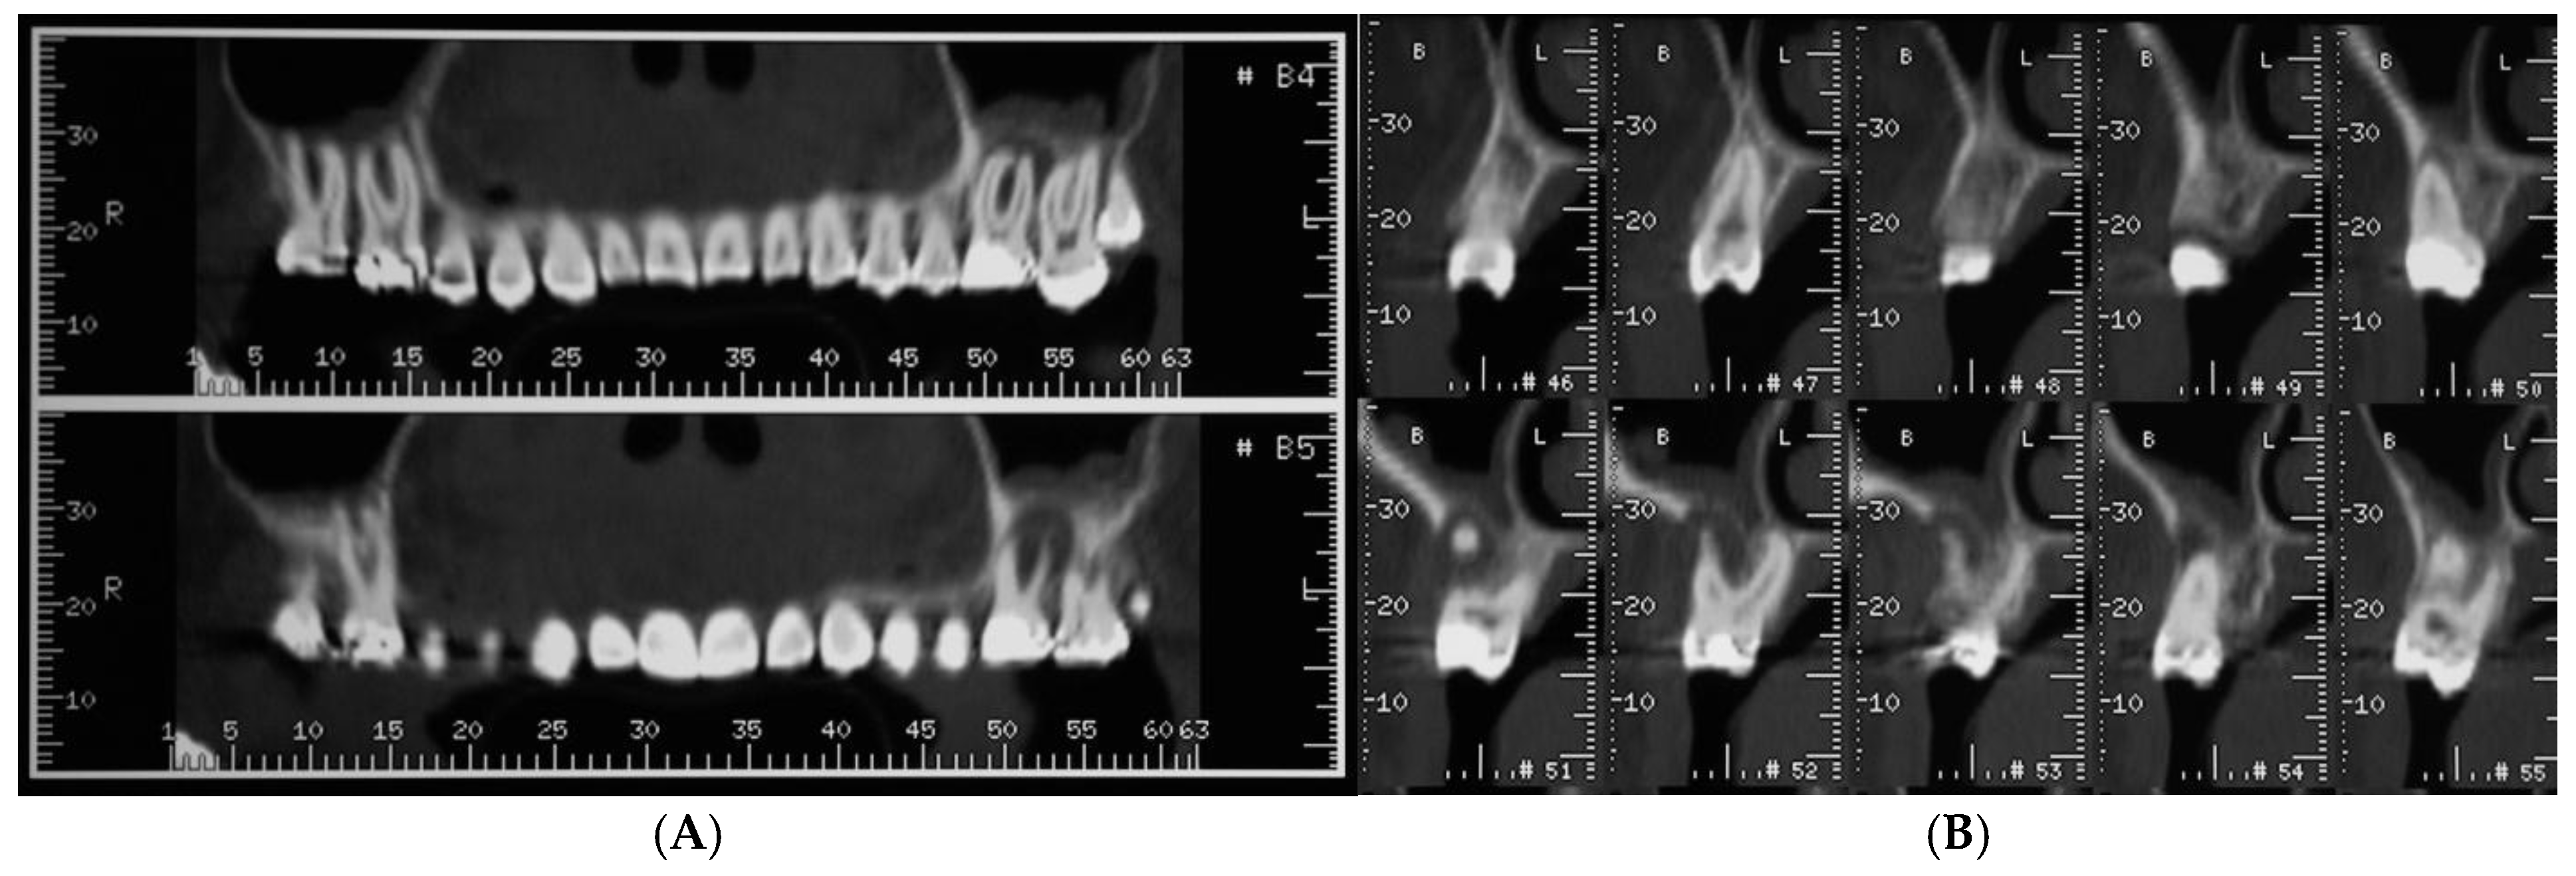

A 22-year-old healthy, non-smoker female patient presented with a chief complaint of recurrent infections of the first maxillary left molar due to a large osteolytic lesion caused by the failure of repeated endodontic therapies, as revealed by computed tomography (CT) scans (Figure 1A,B).

Figure 1.

Computed tomography (CT) scans revealed large osteolytic lesion of first maxillary left molar caused by failure of repeated endodontic therapies (A). Cross-sections showing buccal bone loss (B).

Treatment options were discussed, and the patient signed a consent form for the tooth extraction and the subsequent augmentation procedure, to be scheduled as a staged approach for implant site development. Four months after the tooth extraction, soft tissue healing reached a proper maturation (Figure 2A,B), and a new CT was requested to evaluate the wound healing and bone availability for implant therapy. The CT scans revealed a horizontal ridge defect (Figure 2C,D–F) that required correction with a staged GBR procedure.

Figure 2.

Soft tissue healing four months after tooth extraction (A,B). New CT was requested to evaluate wound healing and current bone availability for implant therapy. CT scans revealed horizontal ridge defect (C–F) that had to be corrected with a regenerative procedure.